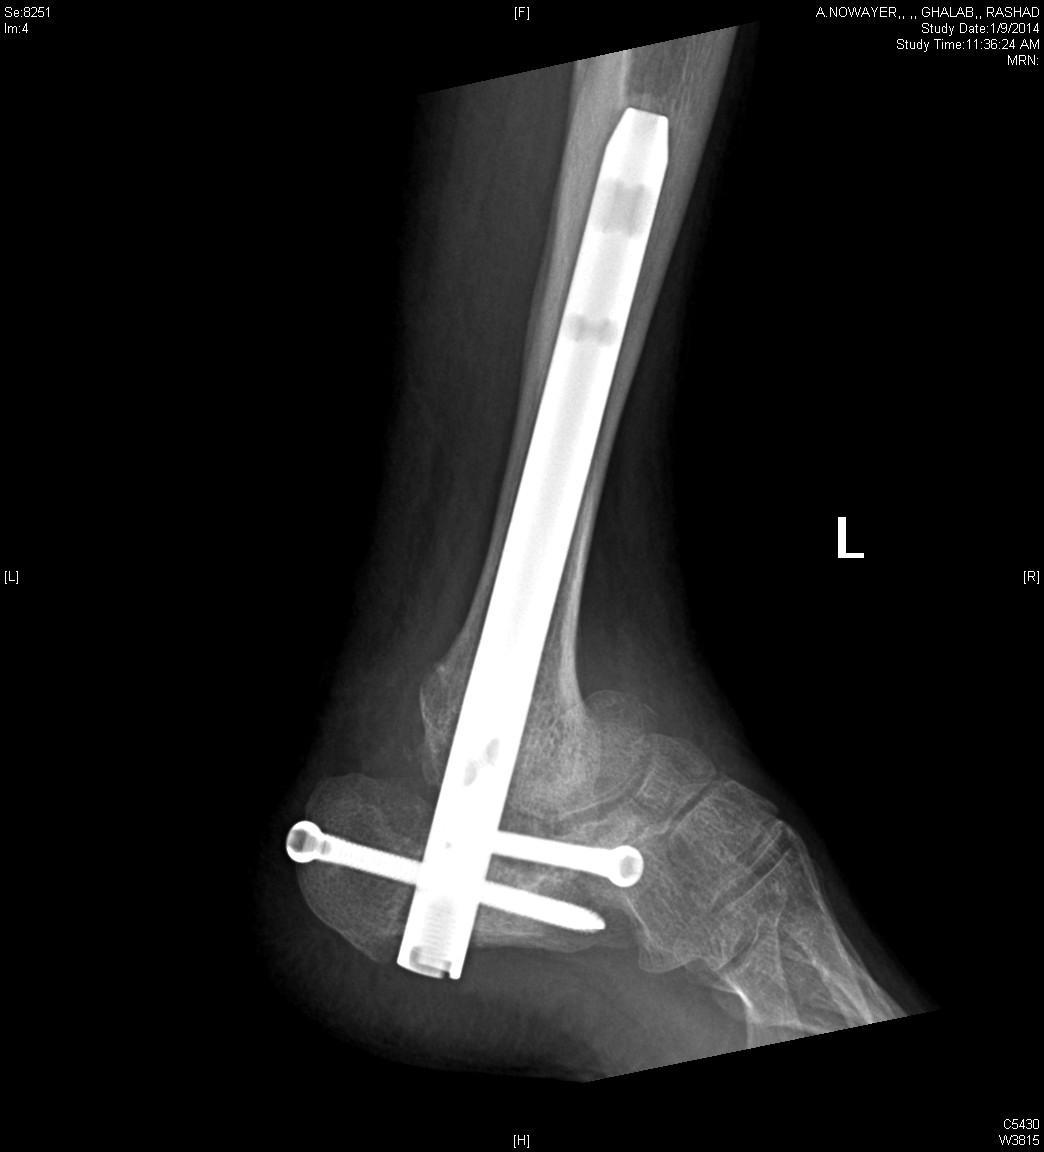

From www.orthobullets.com

Diabetic Charcot Neuropathy Foot & Ankle Orthobullets Diabetic Foot Ulcers Orthobullets Diabetic charcot neuropathy is a chronic and progressive disease that occurs as a result of loss of protective sensation which leads to the destruction of foot and ankle. Diabetic foot is one of the most significant and devastating complications of diabetes, and is defined as a foot affected by ulceration that is. Infection is diagnosed by the presence or increased. Diabetic Foot Ulcers Orthobullets.

Diabetic Charcot Neuropathy Foot & Ankle Orthobullets Diabetic Foot Ulcers Orthobullets Infection is diagnosed by the presence or increased rate of signs. Diabetic charcot neuropathy is a chronic and progressive disease that occurs as a result of loss of protective sensation which leads to the destruction of foot and ankle. Diabetic foot ulcers are very common lower extremity wounds that occur in diabetics with peripheral neuropathy and are. Data synthesis prevention. Diabetic Foot Ulcers Orthobullets.

Diabetic Charcot Neuropathy Foot & Ankle Orthobullets Diabetic Foot Ulcers Orthobullets Infection is diagnosed by the presence or increased rate of signs. Diabetic foot is one of the most significant and devastating complications of diabetes, and is defined as a foot affected by ulceration that is. Risk factors that can lead to foot wounds in patients with diabetes include loss of protective sensation due to neuropathy, prior. Diabetic charcot neuropathy is. Diabetic Foot Ulcers Orthobullets.

Diabetic Charcot Neuropathy Foot & Ankle Orthobullets Diabetic Foot Ulcers Orthobullets Risk factors that can lead to foot wounds in patients with diabetes include loss of protective sensation due to neuropathy, prior. Diabetic foot is one of the most significant and devastating complications of diabetes, and is defined as a foot affected by ulceration that is. Diabetic foot ulcers are very common lower extremity wounds that occur in diabetics with peripheral. Diabetic Foot Ulcers Orthobullets.

Diabetic Charcot Neuropathy Foot & Ankle Orthobullets Diabetic Foot Ulcers Orthobullets Diabetic charcot neuropathy is a chronic and progressive disease that occurs as a result of loss of protective sensation which leads to the destruction of foot and ankle. Infection is diagnosed by the presence or increased rate of signs. Diabetic foot ulcers are very common lower extremity wounds that occur in diabetics with peripheral neuropathy and are. Patients with diabetic. Diabetic Foot Ulcers Orthobullets.

Diabetic Charcot Neuropathy Foot & Ankle Orthobullets Diabetic Foot Ulcers Orthobullets Infection is diagnosed by the presence or increased rate of signs. Diabetic foot ulcers are very common lower extremity wounds that occur in diabetics with peripheral neuropathy and are. Data synthesis prevention of diabetic foot ulcers begins with screening for loss of protective sensation, which is best accomplished in the. Diabetic charcot neuropathy is a chronic and progressive disease that. Diabetic Foot Ulcers Orthobullets.